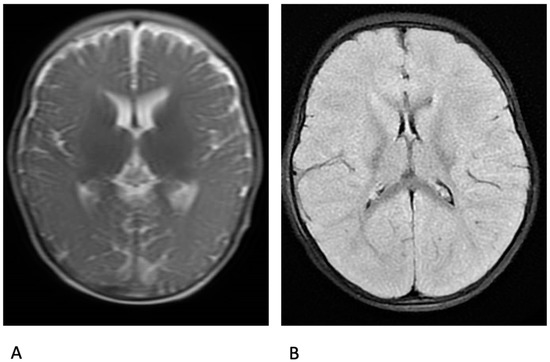

| 6 | F | 5 | 2.3 | c.1837C>T (p.Arg613*) | GTC, monthly, long lasting; focal, rare, brief | VPA, CLB, STP, CLZ | Yes | MDZ, DZP, CLZ PHT | RSV infection | (25 days) | 42 | MRI: significant cytotoxic oedema in the grey matter and cortex | Oromucosal MDZ, CZP; PHT; MDZ; propofol; LEV; KD |